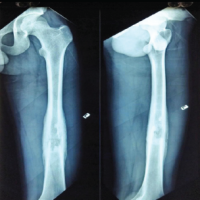

A 16-year-old boy presented to our outpatient department with a history of recurrent patellar dislocation in his right knee for the past 3 years. He also complained of a deformity of his right knee. On examination, his patella was grossly unstable, dislocating at about 30° of knee flexion (Fig. 1). Whole limb X-ray revealed a lateral mechanical axis deviation of 30 mm from the neutral (normal range – <10 mm) (Fig. 2). The opposite limb was normal. The Q angle of the right lower limb was measured to be 22°, which was abnormal (normal range 13–18°). The right knee was in valgus with a tibio-femoral angle of 15° (Fig. 3). The mechanical medial proximal tibial angle was 87.8° which was normal (normal range 85–90). However, the mechanical lateral distal femoral angle was 81°, which was abnormal (normal range 85–90) (Fig. 4 and 5). Hence, it was the distal femur that contributed to the genu valgum. The tibial tubercle–trochlear groove distance was 17 mm, which was normal (normal – under 20 mm), signifying that there was no rotational deformity. The Insall-Salvati ratio was 1.2, which was also normal (range – 0.8–1.2). Magnetic resonance imaging (MRI) revealed a Dejour Type D trochlea dysplasia (Fig. 6) with a trochlear depth of 1.2 mm (normal >3 mm) and a sulcus angle of 172 (normal <140). MRI also revealed an MPFL tear. The factors contributing to the patellar instability were recognized as the unacceptable genu valgum, trochlear dysplasia, and the MPFL tear. Considering that the patient had attained skeletal maturity and to avoid multiple procedures, a decision was made to correct all the anatomical abnormalities as a single procedure.